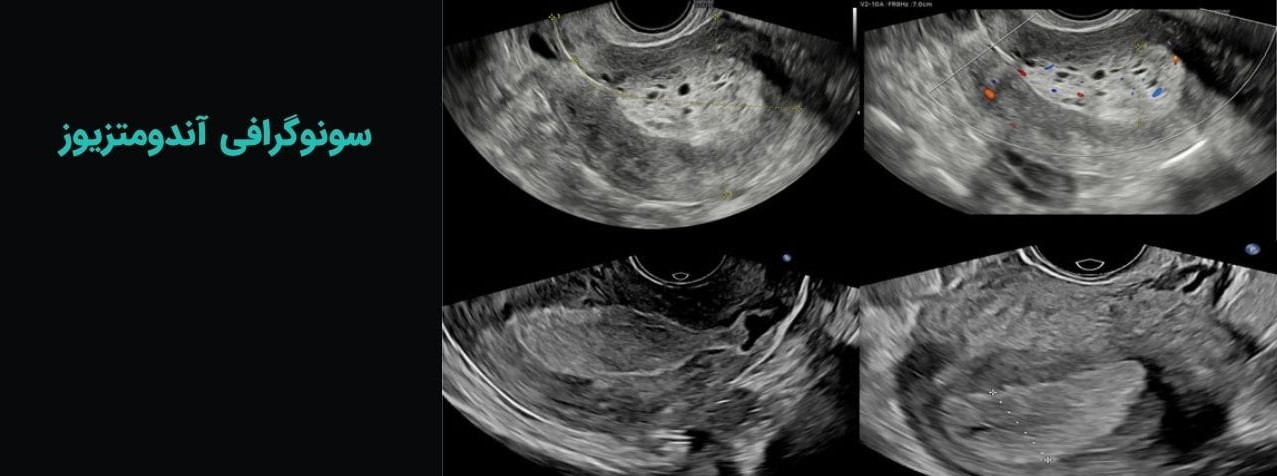

انواع سونوگرافی اندومتریوز

سونوگرافی آندومتریوز در تهران و سایر نقاط کشور، معولاً به سه روش زیر انجام میشود:

سونوگرافی ترانس واژینال، سونوگرافی رکتال و سونوگرافی ترانس آبدومینال.

در سونوگرافی اندومتریوز، شناسایی تفاوت بین یافتههای طبیعی و غیرطبیعی اهمیت بالایی دارد. از جمله یافتههای طبیعی میتوان به دیواره رحم صاف و منظم، فولیکولهای سالم تخمدان، ضخامت طبیعی بافت رحم و جریان خون مناسب در لگن اشاره کرد. این موارد نشاندهنده عملکرد طبیعی سیستم تولیدمثلی هستند و عدم وجود ضایعات غیرطبیعی را تایید میکنند.

در مقابل، ضایعات اندومتریوز معمولاً به صورت کیستهای خونریزیدهنده (Endometriomas)، ضایعات اکوژنیک و تودههای کوچک با بافت ضخیم شده در نواحی لگن دیده میشوند.

این ضایعات میتوانند در تخمدانها، لگن، بافت پشتی رحم و حتی بین روده و مثانه قرار بگیرند و بسته به عمق و اندازه، شدت بیماری را تعیین کنند.

علاوه بر شکل و اندازه، موقعیت ضایعات و ارتباط آنها با ساختارهای مجاور نیز اهمیت دارد؛ زیرا این اطلاعات برای برنامهریزی جراحی یا درمان دارویی حیاتی است.